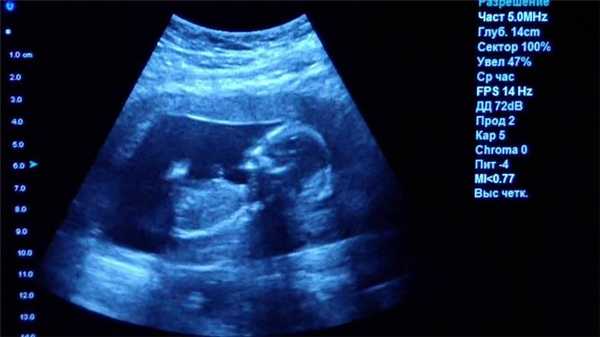

УЗИ - классический метод, который дает огромное количество информации, к тому же абсолютно безопасный. Сейчас он часто используется как дополняющий к другим более «тяжелым методам диагностики». Очень многое зависит от аппарата и врача, который проводит исследование. Высококвалифицированный специалист ультразвуковой диагностики на аппарате последнего поколения действительно может заподозрить опухолевый процесс на самой начальной стадии. Но окончательный онкологический диагноз ставится только по гистологическому заключению. Для этого хирург должен взять образцы ткани «подозреваемого» органа, а морфолог посмотреть, то что происходит в клетках ткани. В будущем, возможно, мы сумеем достичь уровня диагностики, сравнимого с гистологией, и без хирургического вмешательства. Но пока это только будущее.

Что покажет УЗИ

Ультразвуковое исследование или УЗИ - это широко распространенный вид обследования, активно применяемый в диагностических центрах СПб. В ходе данной процедуры диагностика проводится с помощью ультразвуковых волн. Проходя через границы тканей различной плотности, ультразвук по-разному отражается от них. Ультразвуковая установка имеет датчик, который посылает ультразвуковой сигнал, а затем фиксирует ответ и переводит его в графическое изображение. Таким способом врачи могут хорошо обследовать:

- органы малого таза;

- органы брюшной полости;

- лимфоузлы и молочные железы;

- мягкие ткани;

- сосудистую систему.

К сожалению, серьезным препятствием для ультразвука являются кости, через которые сигнал пробиться не может. Поэтому малоинформативным является

- УЗИ головного мозга

- УЗИ сердца

- УЗИ органов средостения

- УЗИ позвоночника.

Основным достоинством УЗИ является отсутствие каких-либо противопоказаний и ценовая доступность. По диагностической ценности и точности УЗИ безусловно уступает МРТ и КТ, однако является приоритетным профилактическим и скрининговым методом обследования для многих заболеваний, включая патологии мочеполовой системы у мужчин и женщин, рака молочных желез и органов брюшной полости, воспалений мягких тканей.

Ультразвуковое исследование (УЗИ)

Главное преимущество такого способа исследования — безопасность. УЗИ можно делать даже беременным женщинам, кроме того, приборы УЗИ-приборы мобильны, их легко можно поставить в палате пациента, чтобы наблюдать за состоянием органов и кровотока в режиме реального времени.

Однако УЗИ не может обеспечить картинку высокой чёткости, поэтому использование этого метода исследование ограничено, например, при помощи УЗИ нельзя диагностировать заболевания ЖКТ.